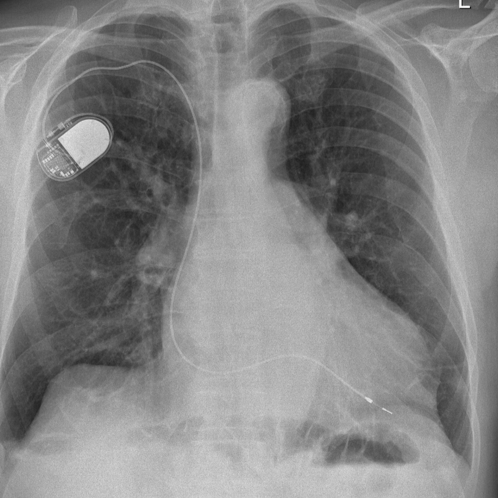

In unserer Klinik werden alle gängigen Arten von Einkammer- und Zweikammer-Herzschrittmachern der führenden Hersteller eingesetzt. Dieser Eingriff ist eine kleinere Operation die zumeist in örtlicher Betäubung durchgeführt werden kann und ca. 30-60 Minuten dauert.

In unseren Katheterlaboren können wir alle verfügbaren ICD´s operativ einsetzen. Die Operation erfolgt ähnlich der Herzschrittmacheroperation. Dabei findet anstelle der normalen Herzschrittmachersonde eine spezielle Defibrillationssonde Anwendung. Das Gerät selbst wird in der Regel unter den großen Brustmuskel in der Nähe des linken Schlüsselbeines eingesetzt.